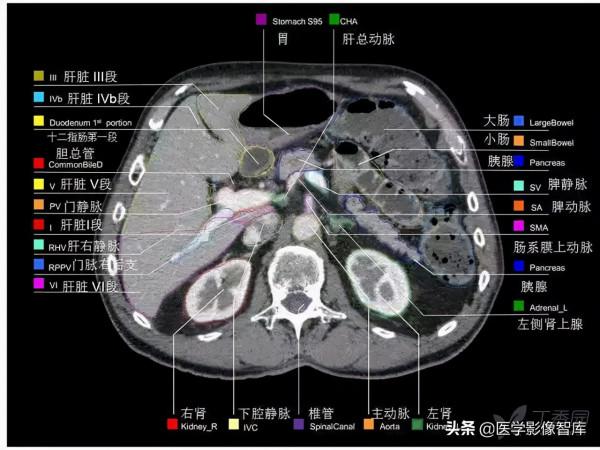

腹部CT